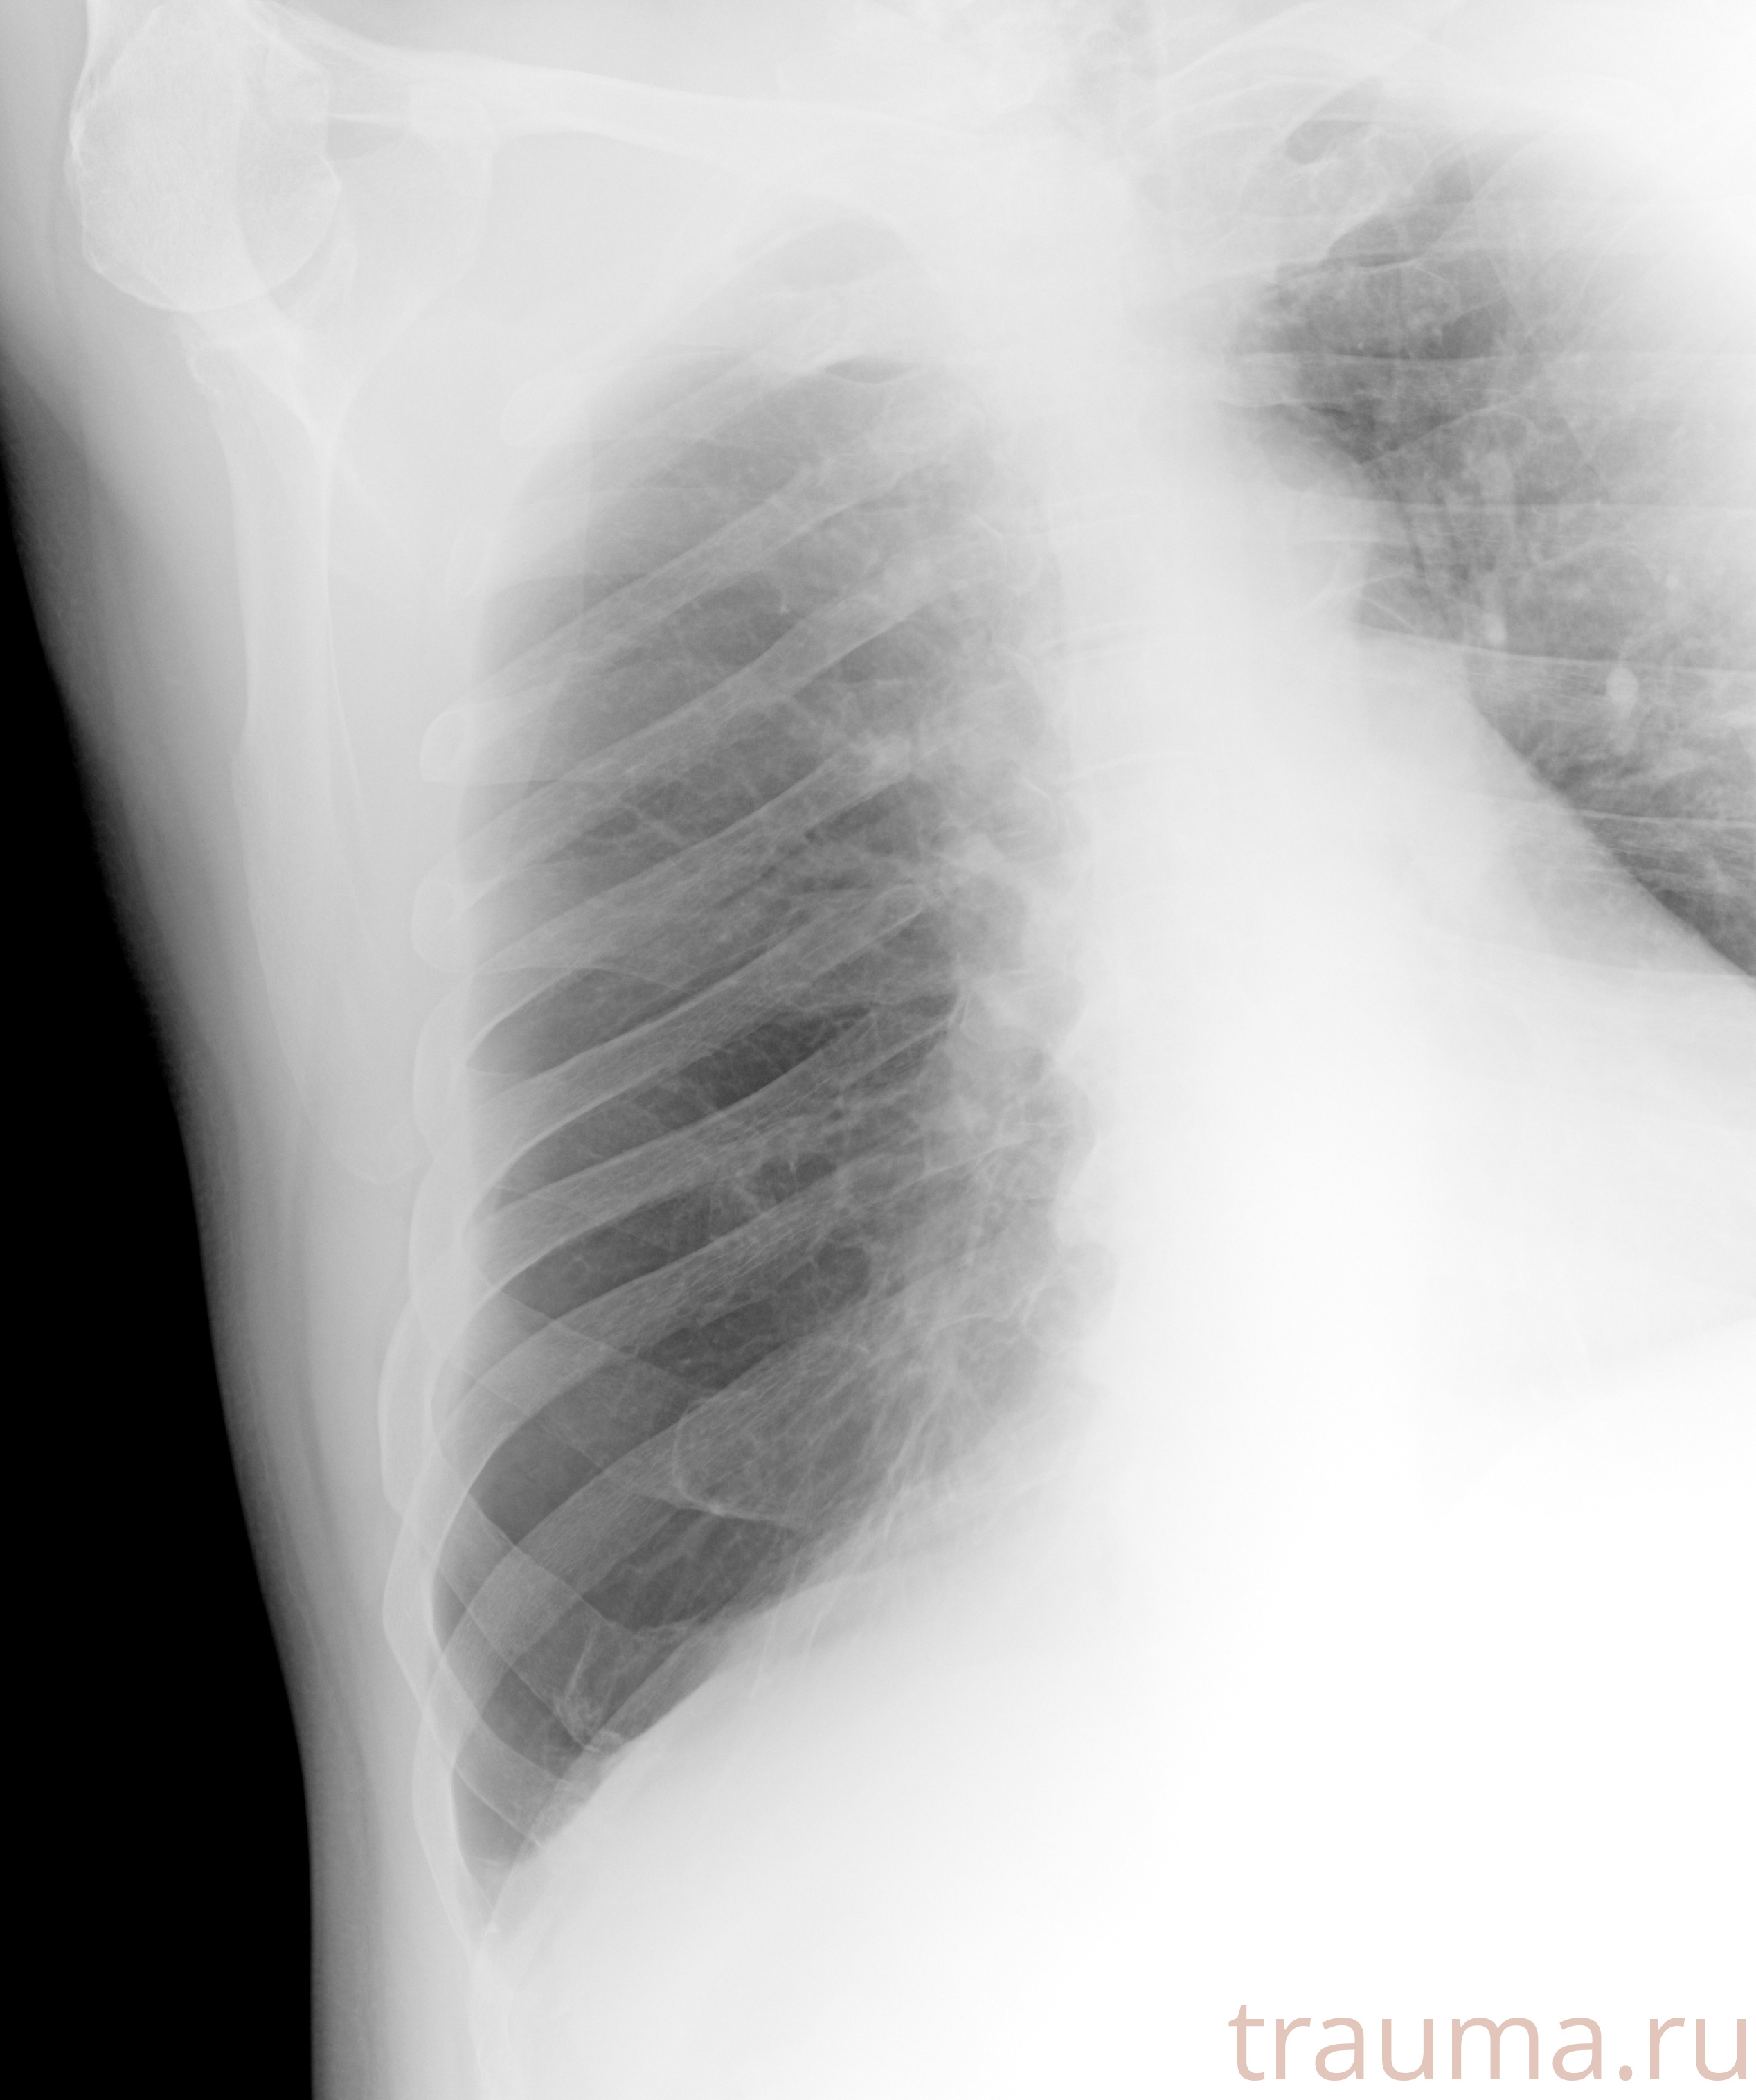

Рентгенограммы

Рентген на дому: по вашему адресу приезжает врач-рентгенолог, травматолог-ортопед с мобильным рентгеновским аппаратом, проводит диагностику травмы или заболевания, делает необходимые рентгенограммы, дает рекомендации по дальнейшему лечению. Получить качественные снимки в домашних условиях возможно благодаря уникальной методике, разработанной МосРентген Центром для института  Склифосовского

при переломе шейки бедра и пневмонии от компании МосРентген Центр - партнера Института имени Склифосовского